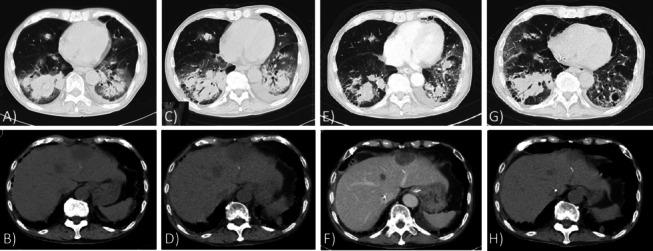

An elderly patient with long-standing RA was admitted to our hospital with acute respiratory failure. Computed tomography upon admission showed diffuse ground-glass opacities superimposed with subpleural reticular shadowing and honeycombing and multiple nodules in the lungs and liver. Despite the discontinuation of MTX and introduction of an immunosuppressive regimen with pulse methylprednisolone followed by a tapering dose of prednisolone and intravenous cyclophosphamide, the patient died due to the acute exacerbation (AE) of RA-related interstitial lung disease (ILD) following the parallel waxing and waning of a diffuse interstitial shadow and pulmonary and liver nodules. At autopsy, RNs were scattered throughout both lung fields in addition to extensive interstitial changes. RNs were also detected in the liver and kidneys. The foci of cryptococcosis were mainly identified in alveolar spaces. Based on the clinical and pathological findings, these nodules were most consistent with ARN because of acute increases in the size and number of previously detected pulmonary nodules.

一位患有长期 RA 的老年患者因急性呼吸衰竭而入院。入院时的计算机断层扫描显示弥漫性磨玻璃影伴胸膜下网状影和蜂巢影,肺部和肝脏有多发性结节。尽管停用了 MTX,并采用脉冲甲基强的松龙联合逐渐减量的泼尼松龙和静脉环磷酰胺的免疫抑制方案治疗,但由于 RA 相关间质性肺病(ILD)的急性加重(AE),患者最终死亡,ILD 的表现为弥漫性间质影以及肺部和肝脏结节的平行消长。尸检时,除了广泛的间质改变外,双肺野还散布着 RNs。肝脏和肾脏也发现了 RNs。隐球菌病的病灶主要位于肺泡腔。基于临床和病理发现,这些结节最符合 ARN,因为先前发现的肺部结节的大小和数量急性增加。